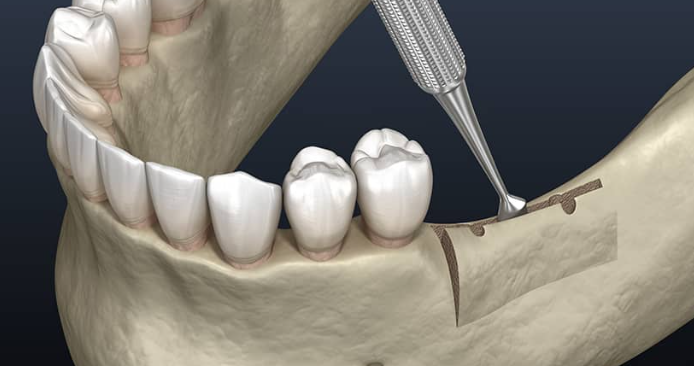

رفع الجيوب الأنفية

تمكين الزراعة في الفك العلوي

إجراء متخصص لرفع أرضية الجيب الأنفي لتوفير ارتفاع عظمي كافٍ في الفك العلوي لنجاح زراعة الأسنان.

الطريقة الجانبية

تقنية تقليدية لتعزيز العظم بشكل كبير

الطريقة من القمة

طريقة طفيفة التوغل لاحتياجات العظم المتوسطة

زراعة متزامنة

رفع الجيب وزراعة الأسنان في آن واحد عند الإمكان